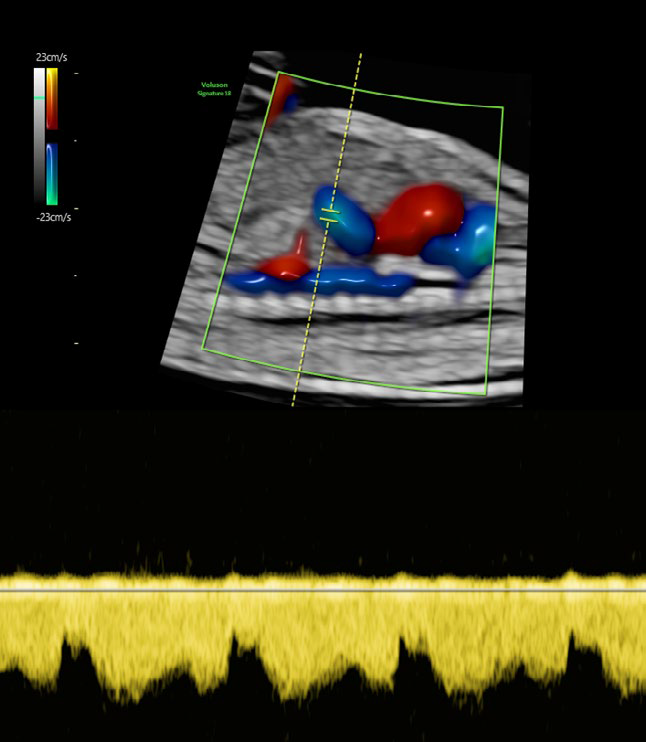

• RadiantflowTM

Separación mejorada entre vasos sanguíneos que proporciona la percepción de un flujo sanguíneo dinámico, añade información de altura y profundidad para una apariencia 3D, Menos destellos, límites vasculares mejorados e Identificación fácil y rápida incluso de los vasos más pequeños.